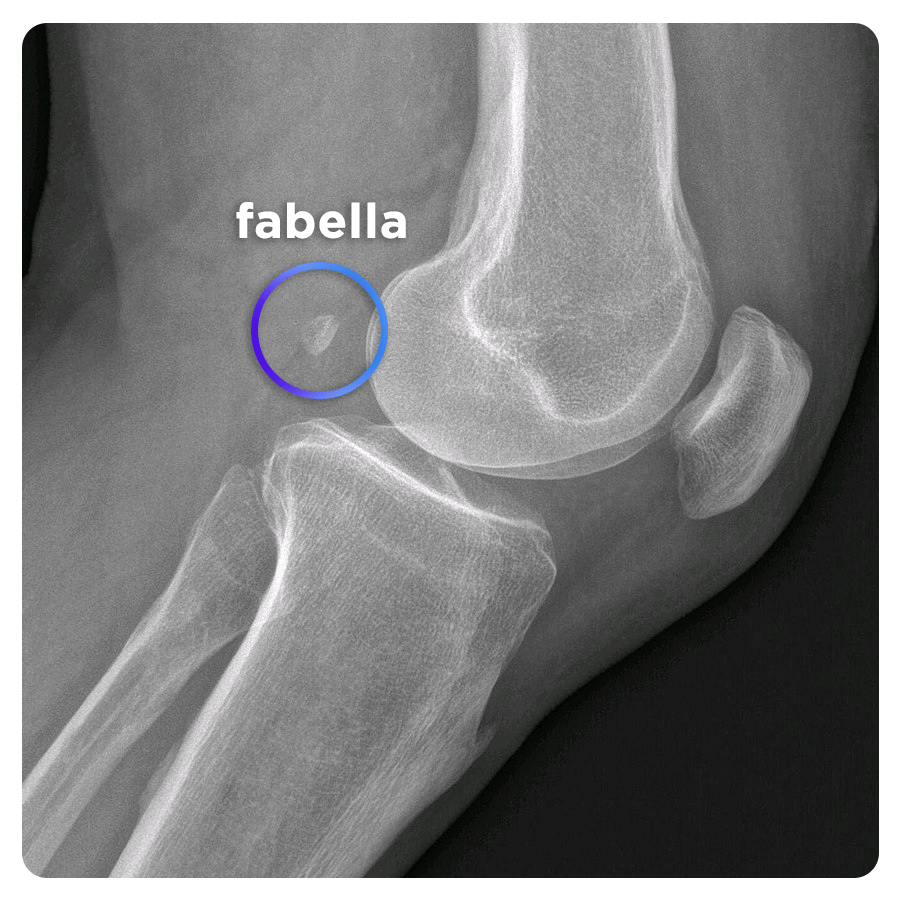

В ходе эволюции некоторые части человеческого тела стали бесполезными, и даже начали исчезать. Яркий пример — кость под названием фабелла, располагавшаяся сзади колена и имевшая крайне маленький размер. У современных людей она встречается крайне редко, поэтому ученые даже не интересовались ее функцией — известно только то, что она часто имеется у людей, страдающих остеоартритом. За последние сотню лет она, по какой-то причине, начала чаще появляться в скелетах людей, из-за чего возникает вопрос — с чем связано ее возвращение?

Она классифицируется как сесамовидная кость — обычно они располагаются в толще сухожилий и примыкают к другим костям. Ученые считают что она, как и другие подобные кости, может служить для уменьшения трения в сухожилиях. При этом, огромное количество людей прекрасно обходится и без нее, поэтому ученые задаются вопросом — с чем связано ее активное возвращение?

Одна из гипотез гласит, что ее возрождение может быть связано с улучшающейся диетой современных людей — по сравнению с жителями прежних веков, современные люди начали лучше питаться, стали выше ростом и набрали вес. Это стало причиной повышенной нагрузки на область колен, из-за чего у некоторых людей и могла вырасти фабелла.

Возможно, эта кость никогда и не исчезала — из-за ее крохотных размеров, вскрытие и рентген попросту не могли ее обнаружить. Теперь же у исследователей есть томографические аппараты, которые легко обнаруживают даже самые маленькие объекты.